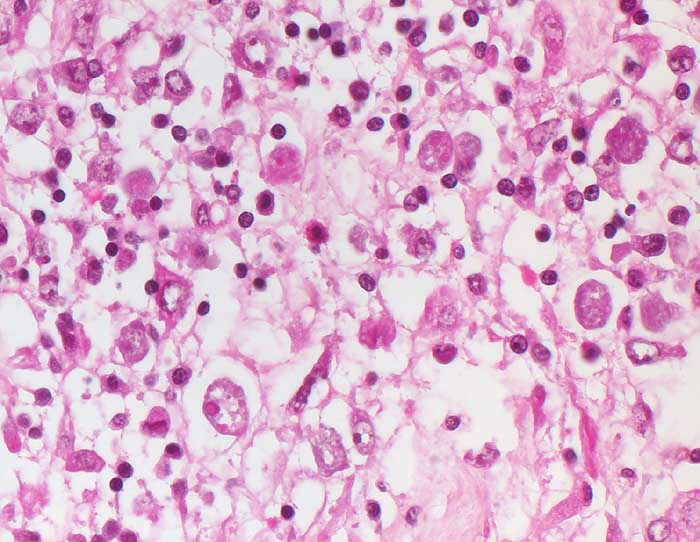

Die gewebsinvasiven Throphozoiten bewirken an der Schleimhautbasis eine Histolyse an der Grenze zur Muscularis mucosae unter Ablösung der Schleimhaut. Bei 90-99% der Infizierten verläuft der Infekt asymptomatisch (intestinale Darmlumeninfektion mit Erregerausscheidung). Die restlichen Patienten leiden an einer invasiven Amöbiasis. Die Krankheit kommt vor allem in den Tropen und Subtropen, seltenerweise aber auch in Mitteleuropa vor. Es gibt ein vegetatives Stadium der Trophozoiten und Zysten, die aus bis zu vier Trophozoiten gebildet werden. Im Dünndarm werden aus ingestierten Zysten Trophozoiten freigesetzt in Form von apathogenen Kommensalen, der Minutaform (12-18 Mikrometer) und der histolytischen Magnaform (bis 20-30 Mikrometer) mit Erythrophagozytose. Die Freisetzung proteolytischer Enzyme bewirkt eine Kolliquationsnekrose. Bei chronischer Ulzeration entwickelt sich ein Amöbom bestehend aus Granulationsgewebe, das den Darm einengen und ein Karzinom imitieren kann. Häufigste Komplikation ist der Leberabszess.